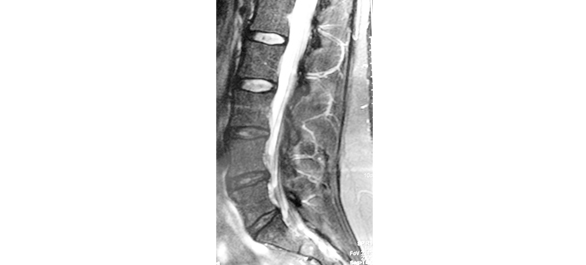

โพรงกระดูกสันหลัง (Spinal canal) คือ ช่องที่มีอยู่ภายในตลอดความยาวของกระดูกสันหลังตั้งแต่ระดับคอไปจนถึงระดับกระดูกใต้กระเบนเหน็บ ภายในโพรงนี้เป็นที่อยู่ของไขสันหลังที่มีความยาวจากกระดูกสันหลังคอจนถึงประมาณกระดูกสันหลังเอวข้อที่ 1 ต่อกับข้อที่ 2 แต่ก็มีรายงานพบการสิ้นสุดของไขสันหลังได้ตั้งแต่ที่ระดับกระดูกสันหลังอกข้อสุดท้ายคือ ข้อที่ 12 หรืออาจยาวลงมาถึงกระดูกเอวข้อที่ 3 ทั้งนี้เมื่อไขสันหลังสิ้นสุดลงแล้ว โพรงกระดูกสันหลังจะเป็นที่อยู่ของเส้นประสาทที่ออกมาจากไขสันหลังที่รวมเรียกว่า Cauda equina

โรคของโพรงกระดูกสันหลังที่พบบ่อยคือ โรคโพรงกระดูกสันหลังตีบแคบ โดยเฉพาะในระดับเอวที่เรียกว่า โรคโพรงกระดูกสันหลังเอวตีบแคบ